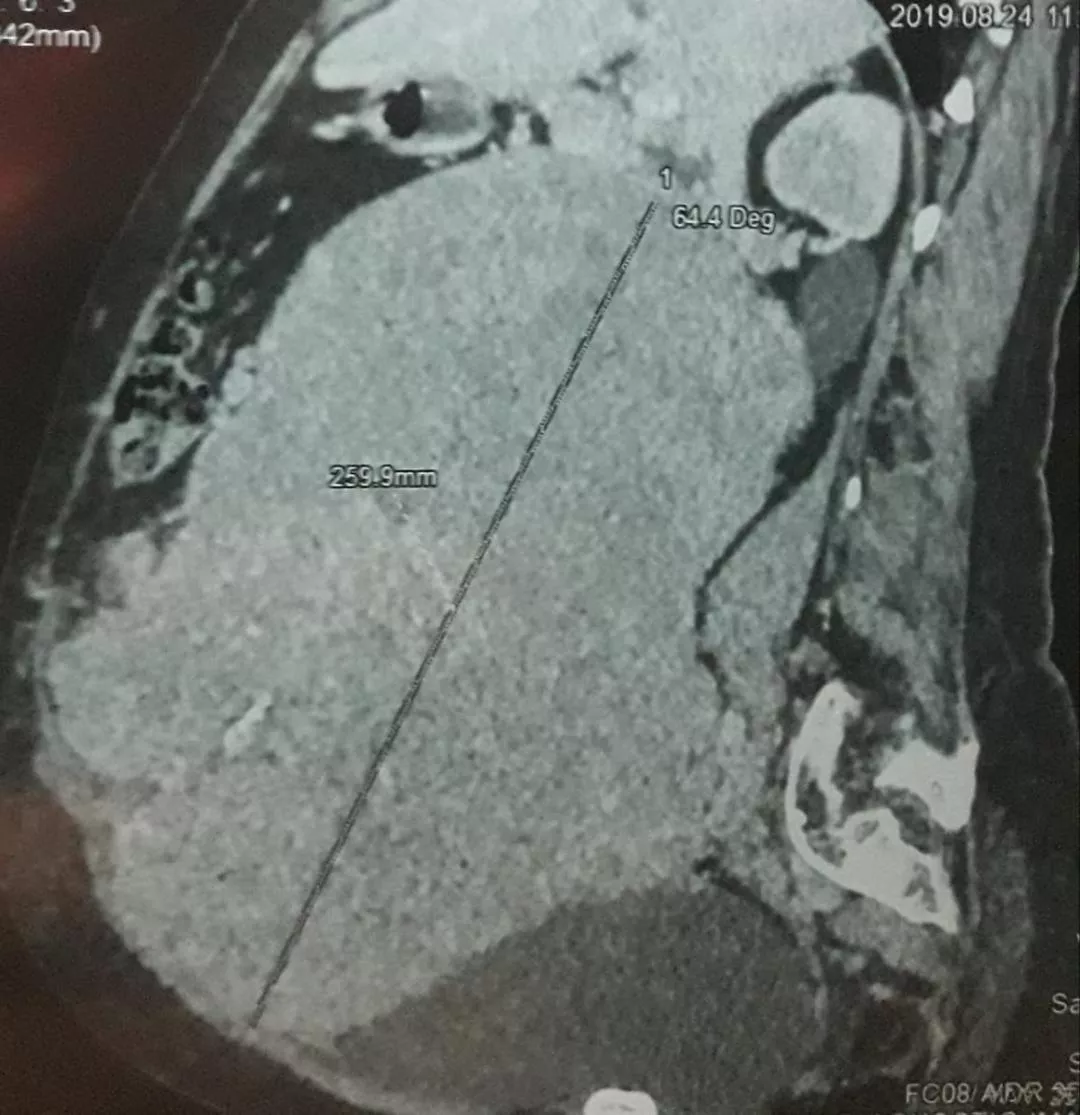

The World Record of “Largest Retroperitoneal tumour removed by surgery “is achieved by the Team of Seven Doctors (Dr. K. Sendhil Kumar, Dr. Piyush Patwa, Dr. Vimalakannan M., Dr. K. Karthik, Dr. Nivedhitha Aarthy, Dr. Venkatachalam and Dr. D. Senthil Kumar) from Coimbatore (Tamil Nadu) India on 2nd September 2019.

The Team successfully removed 7 kilograms weighing cancer tumour "Retroperitoneal Sarcoma” in 7 hours long surgery and set a new World Record for International Book Of Records.

A lady patient who was carrying a tumor for 2 years had undergone surgery at Gateway Hospitals on September 2nd, 2019. The organs were removed as a single specimen involving the right kidney, right ureter, right ovary, right colon (Cecum and ascending colon), ileum, retroperitoneal tumor, and lymph nodes. The patient survived after the major surgery.